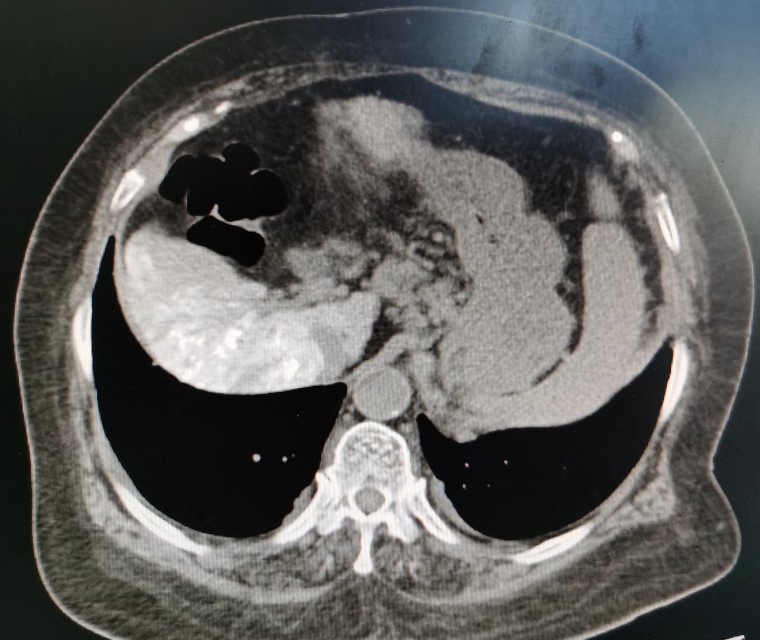

栓塞后的影像图

第一次肝动脉导管栓塞化疗术后,黄婶出现了严重的高热、腹胀和肝肾功能不全,经各种治疗后大概1周左右病情基本稳定。这次保驾护航成功以后,黄婶每次治疗都来找我,哪儿都不去,弄得我压力山大。